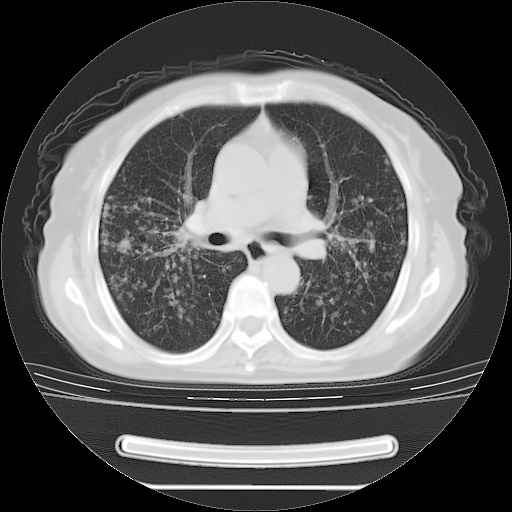

ct示两肺粟粒状病灶,以两肺上叶尖后段及下叶背段分布为主;首先考虑结核。请战友们分析。

两肺内病灶呈小结节状和树芽状,纵膈的肿大的淋巴结密度不均匀,并见有钙化,考虑为两肺结核可能更大些。

两肺内病灶呈小结节状和树芽状,纵膈的肿大的淋巴结密度不均匀,并见有钙化,多形态病灶,考虑为两肺结核,肝内考虑小囊肿。

片子很好,质量很高,两侧肺门淋巴结肿大并有钙化,两肺弥漫病灶,首先考虑tb并播散,但年龄大了呀(72岁)小细胞肺癌不能除外,如果是肺癌也没什么大的治疗了,建议正规抗结核治疗后复查